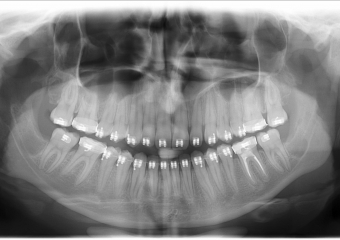

Rx Panoramico inicial - Clínica Cliniface

Rx Panoramico inicial